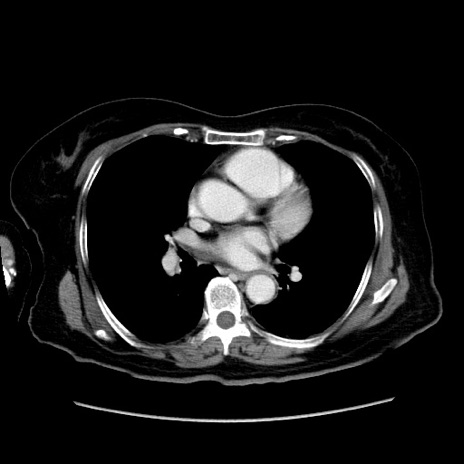

症例19(横断像)

【症例】80歳代女性

【主訴】下腹部痛

【現病歴】約8時間前より下腹部痛の出現あり、救急外来受診。

【既往歴】両側付属器切除

【身体所見】意識清明、下腹部正中に手術痕あり、その部位に一致して圧痛と反跳痛あり。腸蠕動音は亢進。

【データ】WBC 9300、CRP 0.15